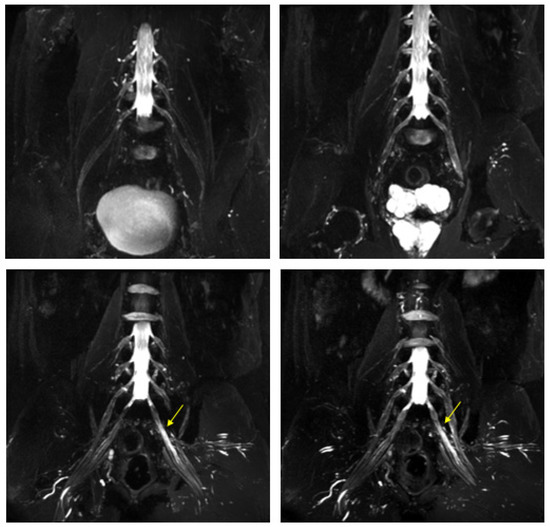

Figure 4.

MR 3D cube nerve images show thickening and T2 hyperintensity of the left obturator nerve (thin arrow in A) and lumbosacral trunk (thick arrow in B) compared to the contralateral one (transverse diameter on left L5 root 7.7 mm (n.v. * 5.99 ± 0.66) and on left S1 root 9.1 mm (n.v. * 5.27 ± 0.53). * Normal values (n.v.) according to the recent study of Su X et al. [20].